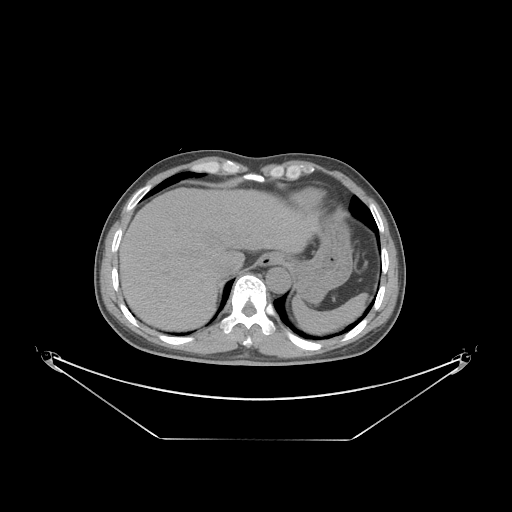

Case Study 2: Liver Contour Segmentation

Deep learning-based methods are also a hot research direction in the liver-related radio-graphic analysis. The first step is usually to segment the contour of the liver. In this case study, we employ a VNet-based neural network, proposed in [64], to segment liver contours.

The public dataset LiTS [48] is used to train the model. This dataset is aimed at the detection and segmentation of the liver and tumors.

VI-1 Workflow

As shown in Fig. 10, the workflow of this case study includes six parts. The “input” part is the source of data, and we use “pre-processing” to convert formats of images. Next, the dataset is split into a training set and a testing set.

The VNet is employed to segment the liver contours from the images and trained with the training set. Then, we use the trained model to initialize the prediction tool of the model to test the testing set. The training loss is visualized with the “loss visualization” tool, while the segmentation results are presented with the “segmentation visualization” tool. The prediction and ground truth are analyzed by computing the “dice score”.

VI-3 Result and Visualization

The network for liver contour segmentation is trained on the LiTS dataset, and the model obtains 0.96 as “dice score”. The dice on the LiTS dataset (testing set) reaches 0.92 as the best performance.

Fig. 12 presents the result of the segmentation task, while Fig. 13a visualizes the training loss as the debugging information.